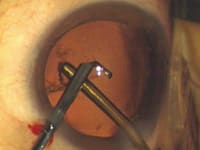

- Dr. Hoffman recommends placing the phaco needle in the eye before the irrigating instrument. He finds that makes insertion easier because there is no fluid pressure working to close the phaco-needle incision. Dr. Olson does the opposite. (See the images on pages 50 and 51.)

Bimanual Microincision Phaco: Key Steps |

||||||||||||||||||||||